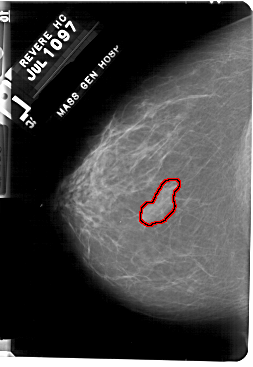

A_1756_1.RIGHT_MLO

RIGHT_CC LINES 5491 PIXELS_PER_LINE 3661 BITS_PER_PIXEL 12 RESOLUTION 43.5 NON_OVERLAY

FILE: A_1756_1.LEFT_CC.OVERLAY

TOTAL_ABNORMALITIES 1

ABNORMALITY 1

LESION_TYPE MASS SHAPE IRREGULAR MARGINS ILL_DEFINED

ASSESSMENT 4

SUBTLETY 4

PATHOLOGY BENIGN

TOTAL_OUTLINES 1

BOUNDARY